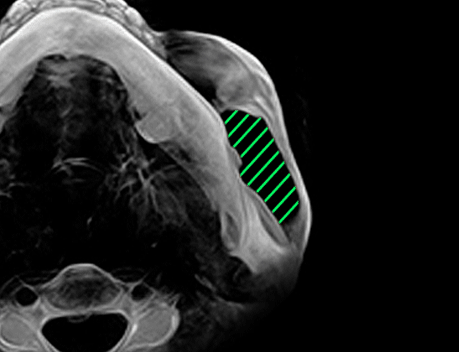

지나치게 많이 잘라낼 경우 굉장히 인위적이고 부자연스러운 개턱처럼 보이게 됩니다.

귀 밑 사각턱은 뼈의 발달한 정도, 귀와 입술의 위치, 남/여 성별,

개인의 선호도에 따라 다르며 1cm에서 4cm까지 남기게 됩니다.

무조건 많이 깎는 것보다

어떻게 깎느냐 가 중요합니다.

지나치게 많이 잘라낼 경우 인위적이고 부자연스러운 개 턱처럼 보이게 됩니다.